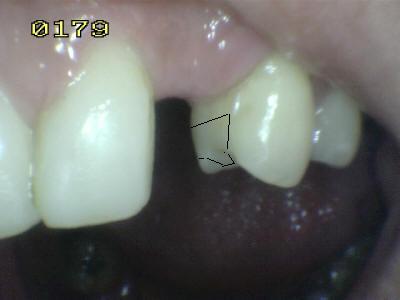

El tallado de un puente Maryland es

similar al tallado para una prótesis parcial removible; e incluso mas

sencilla porque solo hay dos piezas dentales pilares, adyacente a la

brecha edéntula, la cual es una sola pieza faltante. Y debe tener un

solo eje de inserción (ver imagen derecha), para esto hay que tallar los

planos guía y los apoyos oclusales. |